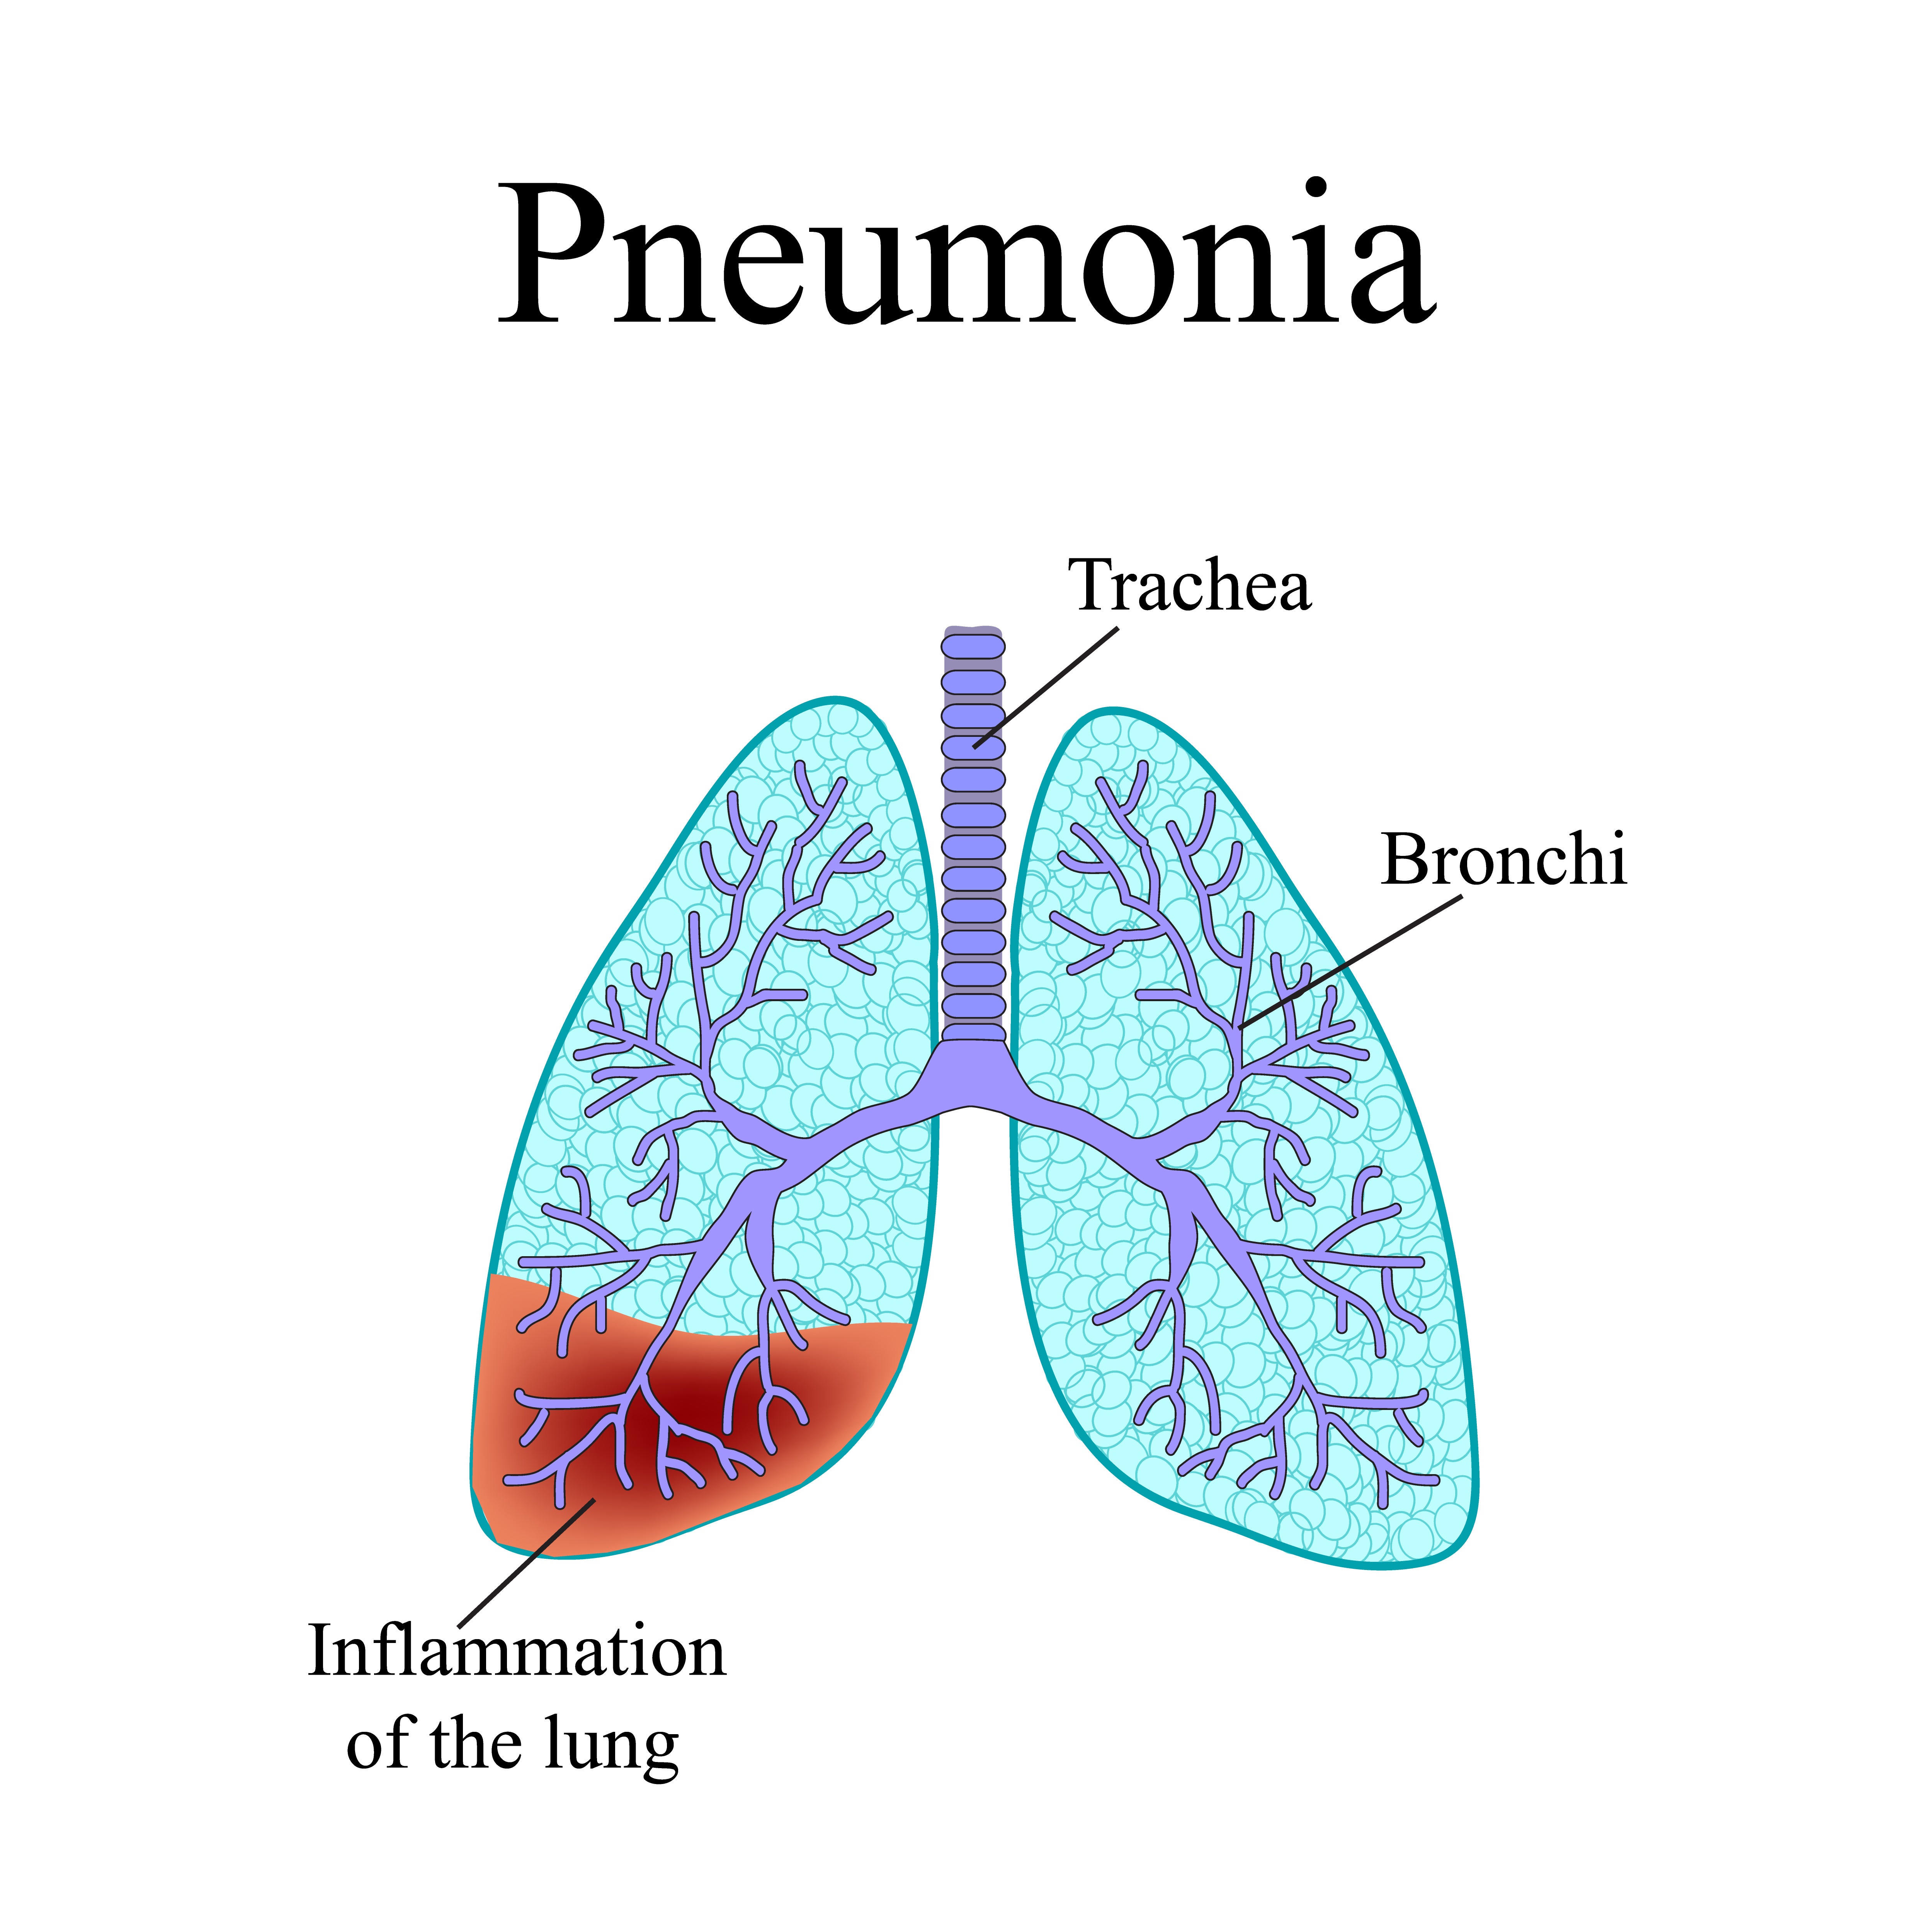

Пневмония - это серьезное заболевание легких, которое может быть вызвано различными причинами, включая бактериальные, вирусные и грибковые инфекции. Для того чтобы наглядно показать симптомы, диагностику и лечение этого заболевания, картинки могут быть очень полезны.

Картинки с симптомами пневмонии

В этом разделе представлены изображения, демонстрирующие различные симптомы пневмонии, такие как кашель, одышка, боль в груди и повышенная температура. Эти картинки могут быть использованы для обучения и презентаций в области медицины и здравоохранения.